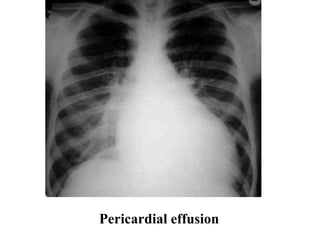

Pericardial effusion